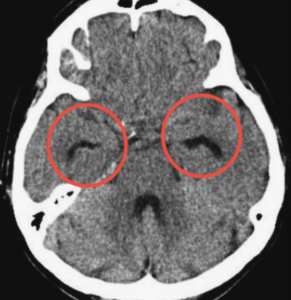

| 検査 | 【画像検査】 頭部CT・MRI:DESHが特徴(不均衡な所見を示す水頭症で、正常圧水頭症に特徴) ①脳室拡大:Evans index 0.3以上、冠状断像で脳梁角90°以上 ![]() ②シルビウス裂拡大 ③高位円蓋部および正中部の脳溝・くも膜下腔の狭小化 ![]() ④側脳室下角の拡大(ニコニコサイン) ![]() |